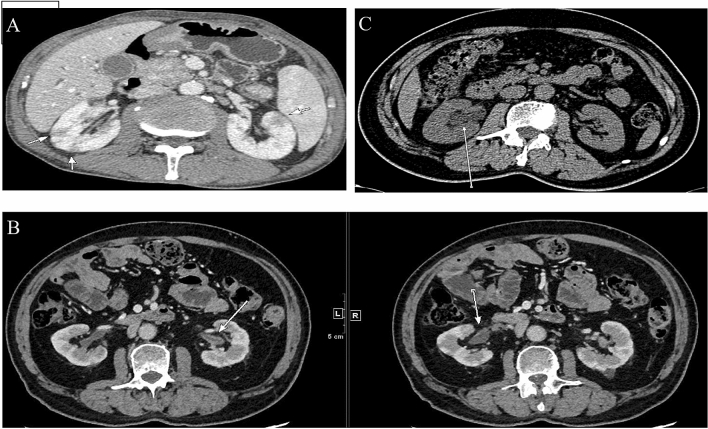

We used contrast-enhanced CT to identify radiological abnormalities in IgG4-RKD+ patients except those with renal dysfunction. Fifty of the 53 IgG4-RKD+ patients exhibited characteristic findings of the kidney radiology. Among them, 14 patients were presented with more than one kind of lesion. The most common finding is multiple, often bilateral, hypodense lesions in 31 (58.5%) IgG4-RKD+ patients, which are called small cortical hypodense nodules (Fig. 4A), followed by thickening of the renal pelvic wall in 18 (34.0%) IgG4-RKD+ patients (Fig. 4B), and ureteric obstruction and hydronephrosis related to RPF in 9 (17.0%) patients who had also other specific kidney lesions of IgG4-RKD+ (Fig. 4C). Besides, diffuse patchy involvement, tumor-like less-enhanced mass and rim-like lesion were observed in 8 (15.1%), 2 (3.8%) and 1(1.9%) patient, respectively.

Figure 4.

Representative contrast-enhanced CT imaging of IgG4-RKD+ . (A) Multiple low-density lesions in the bilateral kidneys (arrows). (B) ureteric obstruction and hydronephrosis related to RPF (arrow). (C) Renal pelvis thickening with smooth intraluminal surface (arrows).

Main abnormalities on renal imaging were revealed in a total of 42 (79.2%) of IgG4-RKD+ patients: multiple low-density nodules, hydronephrosis and thickening of renal pelvic wall. Similar with previous studies, there were also some other imaging manifestations in our cohort, including diffuse patchy involvement of the bilateral kidneys and rim-like lesion of the kidney11,22. CT was the most common mode of renal imaging, including PET-CT, which is increasingly used. PET-CT could contribute to excluding malignancy with little radiative damage. Moreover, PET-CT is helpful for discovering the involvement of some silent lesions, however, its cost should also be taken into account.